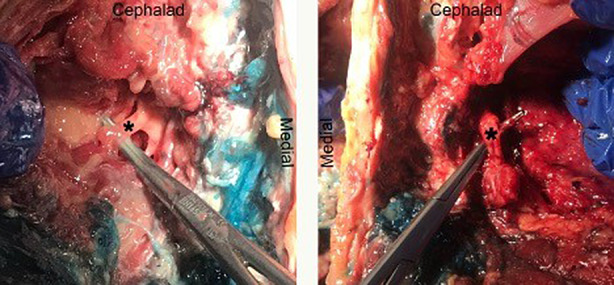

A bilateral L4 ESPB was successfully performed at L4 in a single cadaver model. Appropriate craniocaudal injectate spread in the plane deep to the lumbar erector spinae muscles was observed using ultrasound (Fig. 1). After posteroanterior plane dissection, the injectate solution was observed to have spread in a craniocaudal direction consistently extending from L2 to the sacrum, bilaterally (Fig. 2). Staining from the methylene blue was found dorsal to the transverse processes at these levels and extending to the inside of the erector spinae muscles, covering the posterior rami. Dissection deep to the erector spinae showed that the dye did not reach the ventral rami of the spinal nerves (Fig. 3). There was no dye present in the subcutaneous layer other than trivial leakage that likely occurred during needle placement. No laminectomy was performed and the epidural space was not dissected.

Fig. 3.

Dissection of ventral rami of L4 spinal nerve showing lack of injectate staining (left: left L4 ventral ramus; right: right L4 ventral ramus)